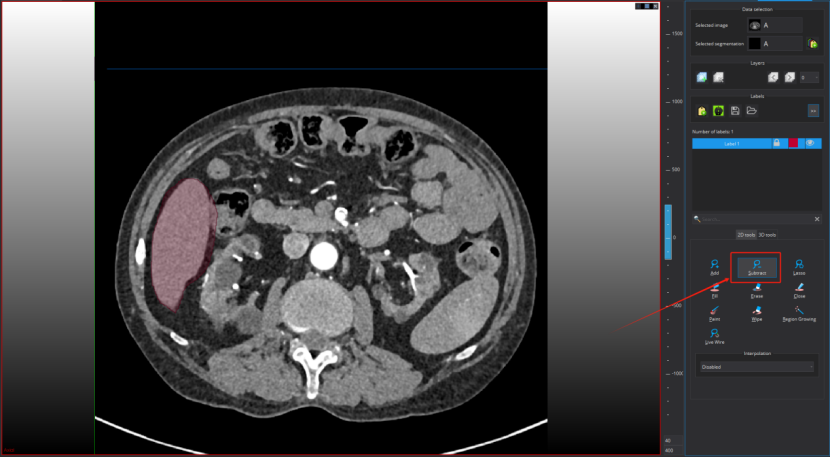

针对问题2:点击下图按钮,然后沿着超出边界部分边缘进行勾画即可消除超出区域(注意:如果是标注不足,则是点击add,对不足区域的边缘进行勾画即可补上不足区域)